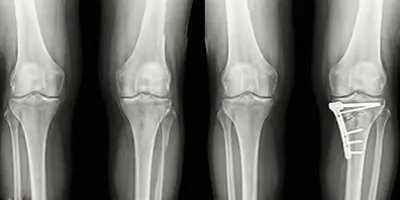

Yüksek Tibial Osteotomi, bacak eğriliği ve diz kireçlenmesi tedavisinde uygulanan, diz protezini geciktiren ortopedik cerrahi yöntemidir. Kimlere uygulanır, nasıl yapılır?